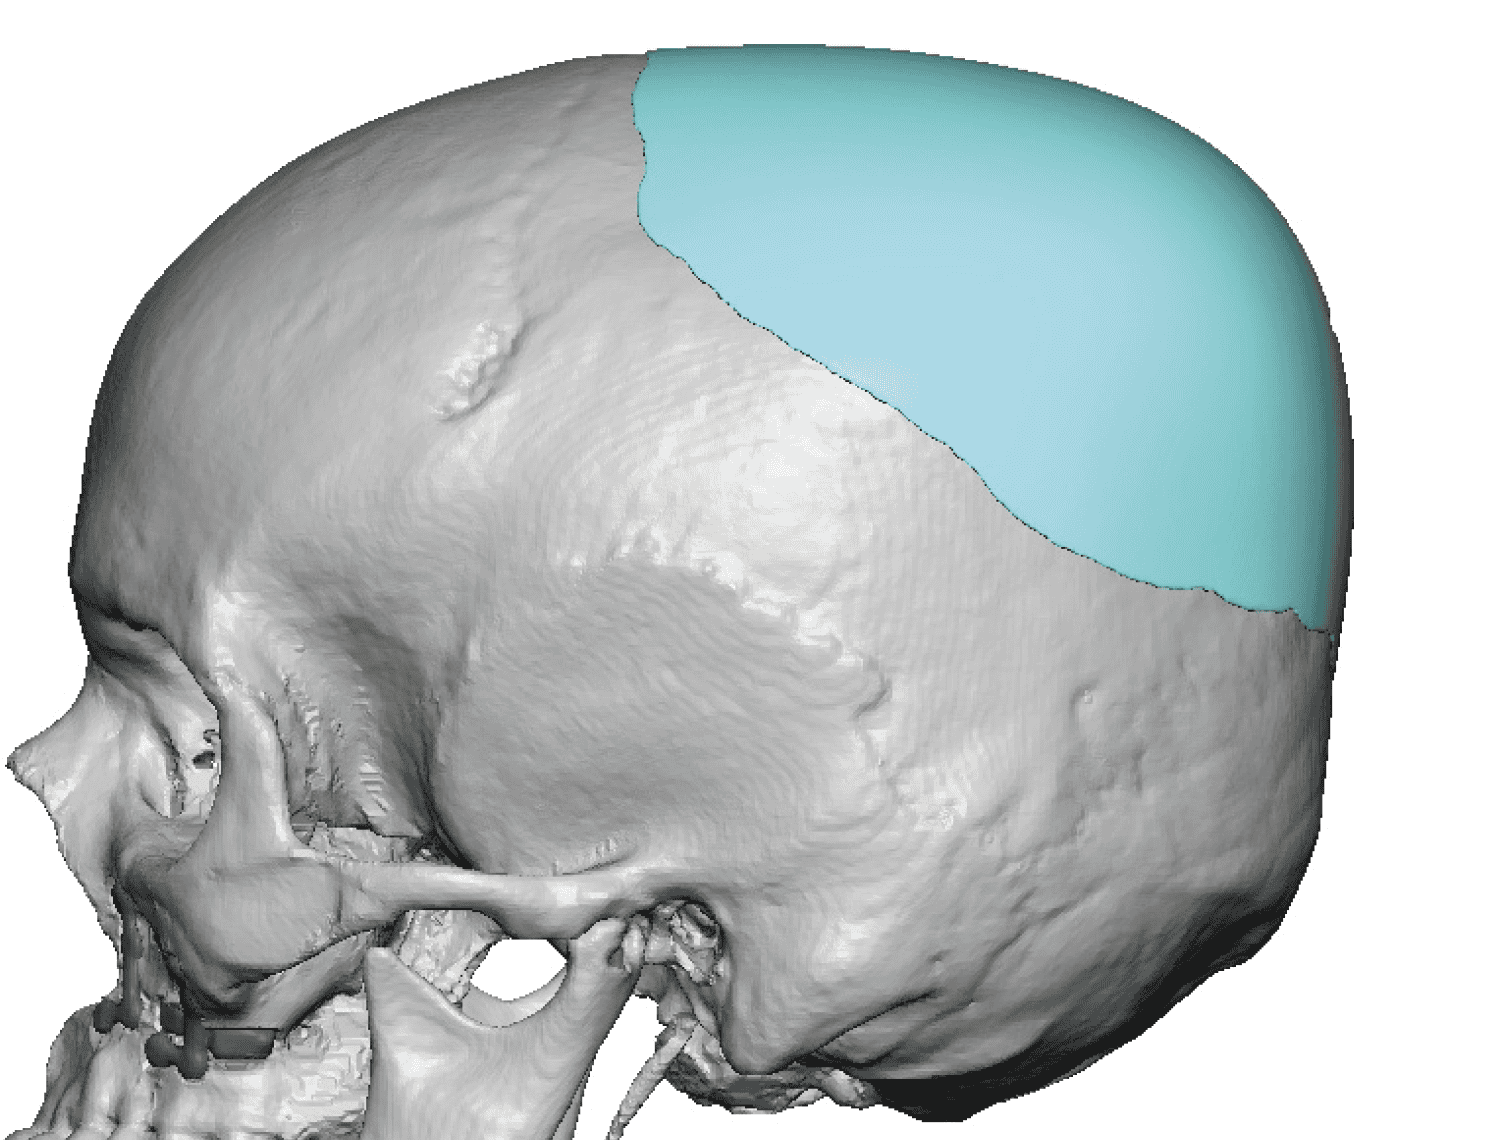

Patient 110

Desire for head shape asymmetry improvement as the final stage of total skull reshaping surgeries. (previous skull implants are in green color)

Placement of custom temporal implant through an incision behind the ear.

Desire for head shape asymmetry improvement as the final stage of total skull reshaping surgeries. (previous skull implants are in green color)

Placement of custom temporal implant through an incision behind the ear.